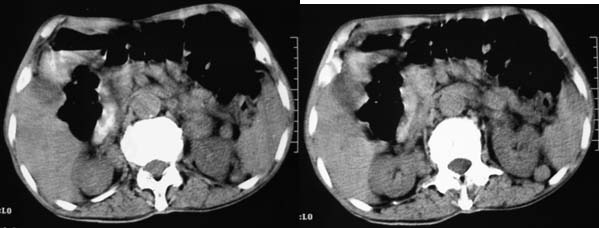

上腹部横断图象显示:心包,胃体小弯侧,肾等器官周围以及肠系膜腹膜后多发的大小不等的小结节样软组织密度影,部分境界不清,未见明显钙化.如此广泛的小结节样影,我认为首先考虑淋巴结肿大.能够引起淋巴结肿大的最常见的原因为:1.炎症(结核常见);2.转移;3.淋巴瘤.其中淋巴结结核不同程度可见钙化,而且这么大范围少见,暂不考虑.

肝胃间隙,双侧肾周间隙,腹主动脉旁类圆形软组织结节影,首先考虑是增大的淋巴结。

双肺及腹膜后多个大小不等的结节影,两侧肾上腺增大,右肾内可见异常密度影,右肾静脉似乎增粗,右肾癌并多处转移 ?肺癌多处转移?建议腹部增强并进一步检查肺部.